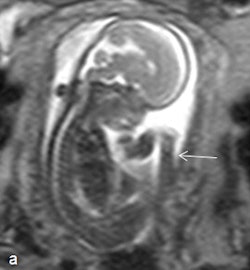

The technique can be useful too in amniotic band syndrome, which comprises a set of fetal malformations secondary to the entrapment of one or more fetal body parts by fibrous bands during gestation. The effects vary from slight indentations in soft tissues to amputation of limbs or fetal death. On fetal MRI, the bands are seen as linear tracts that are hypointense in T2-weighted images, reportedly identifiable in 57% of cases, and amputation and/or malpositioning of the limbs are visible, they stated.